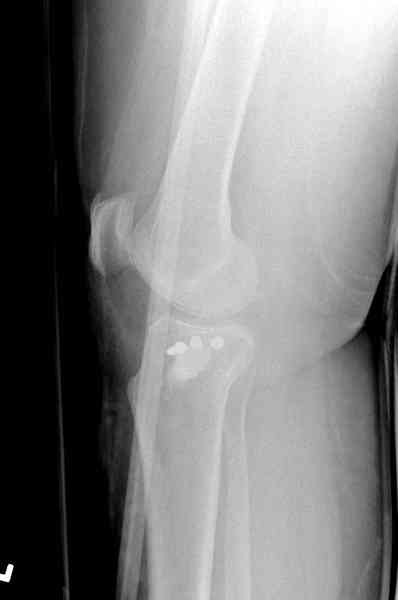

Здравствуйте, уважаемые коллеги!Подскажите, пожалуйста, какой выбрать доступ и способ фиксации при импрессионном переломе заднего отдела наружного мыщелка большеберцовой кости. Женщина 40 лет, травму получила 02.01.2008, катаясь на горных лыжах.Есть ли здесь необходимость использовать задний доступ, или можно справиться через наружный? Есть ли шансы сделать закрыто - под ЭОП через медиальное "окошко" поднять забойником суставную поврехность? Какой лучше использовать фиксатор?Спасибо.

центральная импрессия, а при ипрессии с краевым переломом - после приподнимания импрессии опорная (Butress) пластина, как на снимке.